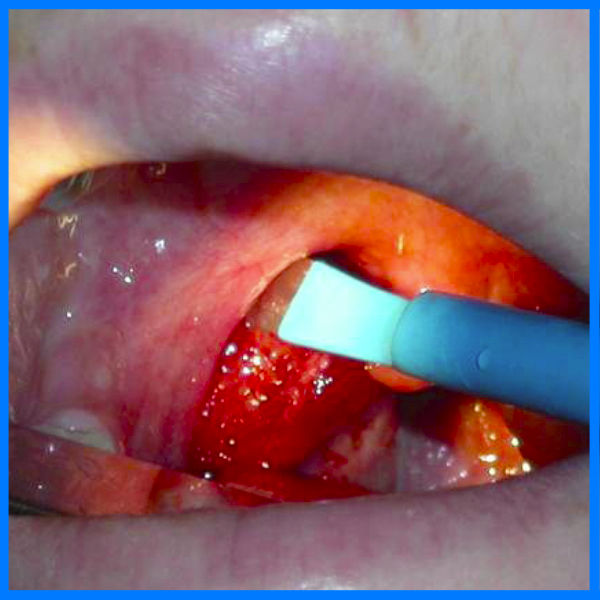

Tonzilloektomiya jarrohlik operatsiyasi

- Tonzillektomiya-bu jarrohlik aralashuv, uning mohiyati Palatin bodomsimon bezlarini olib tashlashdir.

Bugungi kunda operatsiya turli usullar va vositalar yordamida amalga oshiriladi. To'qimalarning shikastlanishini, tiklanish davrining davomiyligini va bemorlarda noqulaylikni kamaytiradigan texnologiyalar faol ravishda joriy etilmoqda. Surunkali tonzillit bilan aralashuv amalga oshiriladi. Tonzillektomiya to'g'risida qaror faqat shifokor tomonidan va individual ko'rsatmalar mavjud bo'lganda qabul qilinadi. Qoida tariqasida, operatsiya faqat konservativ terapiya bemorning tiklanishiga va uning ahvoli sezilarli darajada yaxshilanishiga olib kelmasa buyuriladi.